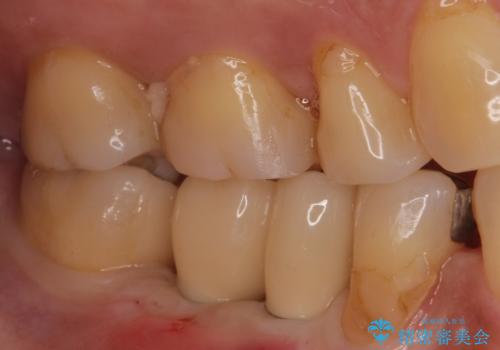

欠損部に1本だけインプラントを埋入しても大きな被せ物になってしまい清掃性が悪くなるので清掃性が良くなるように2本小臼歯用のインプラントを埋入しました。

また1番奥の歯はセラミックインレーで治療を行いました。